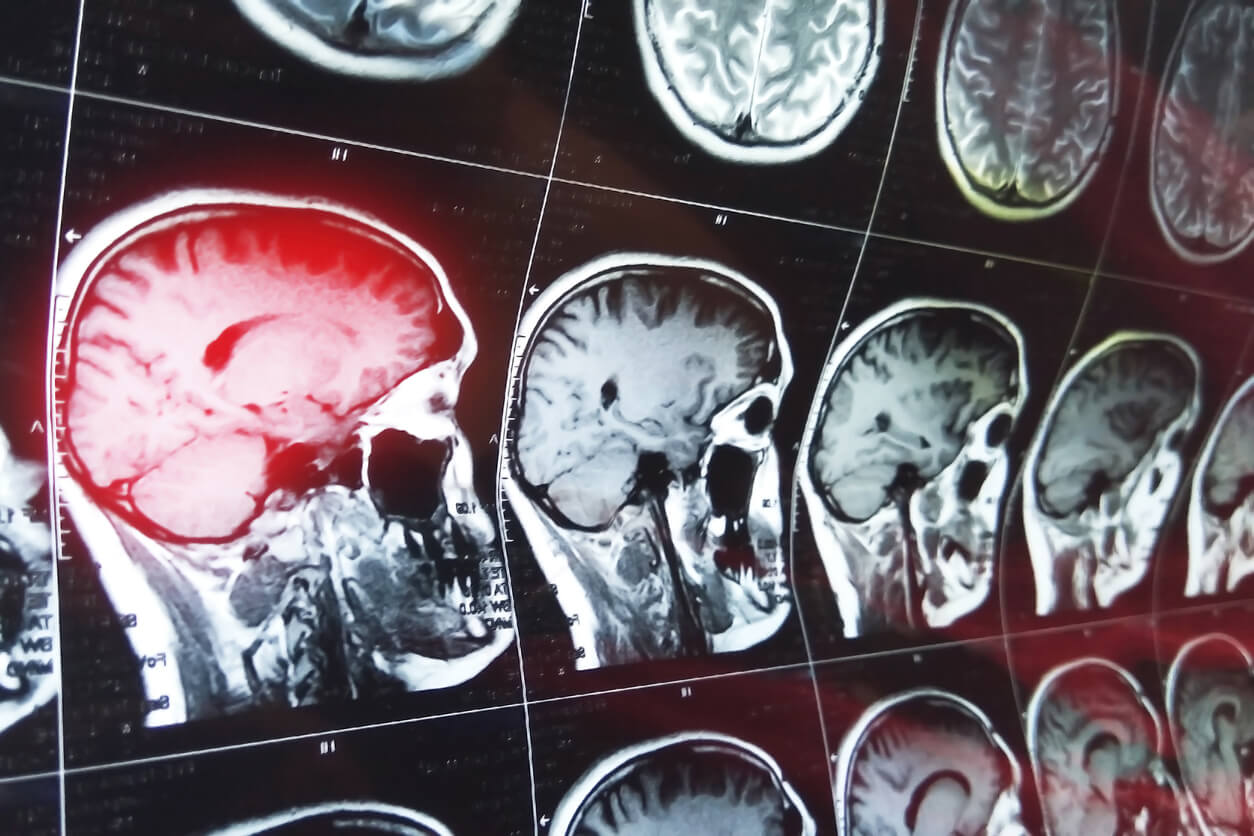

There is a growing concern in Australia and internationally about the incidence of sport-related concussions and the potential health ramifications. A concussion is a brain injury, a complex physiological process that affects the brain, induced by external forces. Trauma may be caused by a direct or indirect blow to the head, face, neck or body, causing an impulsive force transmitted to the head.

Concussion involves short-lived impairment of neurological function and is an evolving injury that may change over hours to days. In most adults, symptoms are typically resolved within the initial fourteen days of injury.